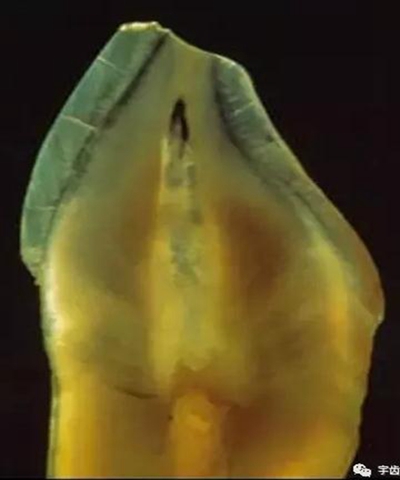

牙體解剖知識(shí)

牙體各個(gè)面的解剖厚度